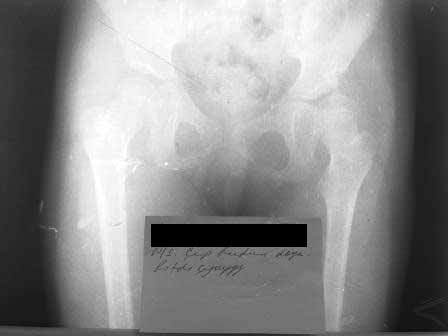

результат через 2 года, но повторяюсь осталось так называемое недопокрытие впадиной головки бедра но клинически результат отличный.

Так может не стоит проводить "фиксация в гаипсе окола полугода далее на шине распорке типа Виленского" с такой исходной Р-картиной? Все показания к выполнению полного объема хирургического лечения (ОВ+КОБ+Salter) с хорошими отдаленными результатами лечения. См. выше названное пособие.